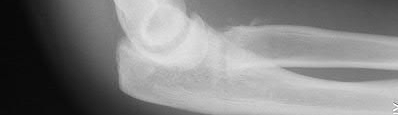

Figure A is an AP radiograph of a posterior knee dislocation. Figure B is a lateral showing the same injury.